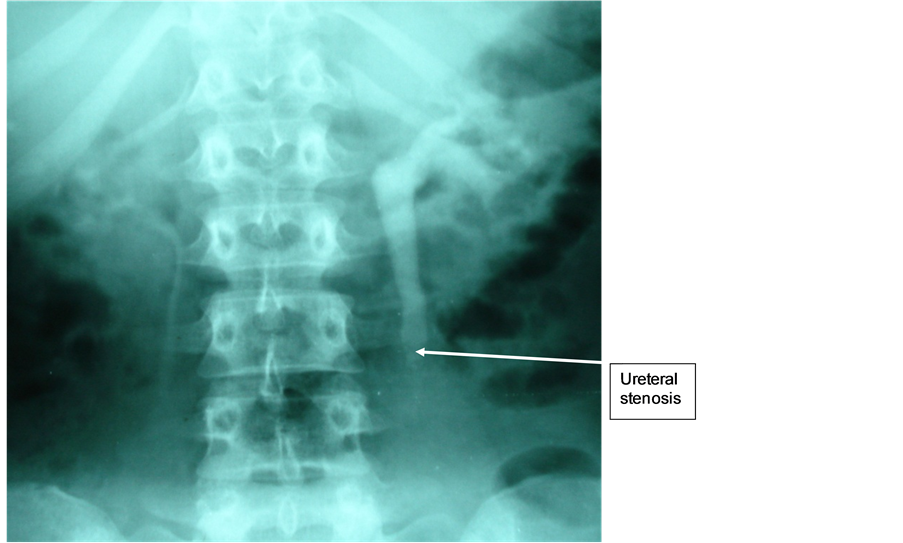

Mrs H.B., 30 years old, with a history of pain in the left iliac fossa, visited for a left renal colic crisis. Physical examination revealed an agitated patient in a good general condition, with normal coloration of the mucous membranes and left iliac fossa sensitivity. Renal function was normal. X-ray of the abdomen without preparation (AWP) didn’t show anything particular. The ultrasound revealed dilated pelvic caliceal cavities in the left kidney. Intravenous urography showed a left ureterohydronephrosis on an obstacle of the left lumbar ureter (Figure 3). The CT scan confirmed a pyelocaliceal and ureteral left dilatation without lithiasis hindrance. The ureteroscopy revealed a stenosing iliac ureter sprouting tumor and biopsy could not be performed because of lack of suitable clamps. An urothelial tumor of the iliac ureter was diagnosed. A nephro-ureterectomy was performed with resection of a bladder flange. Histological examination concluded to a papillary carcinoma (PT1G2) of the left ureter with a discrete interstitial tubulonephritis. Follow-up biological and radiological examinations at 6 months and two years were normal.

Figure 3. Left neoplastic uretero-hydronephrosis of the iliac ureter.